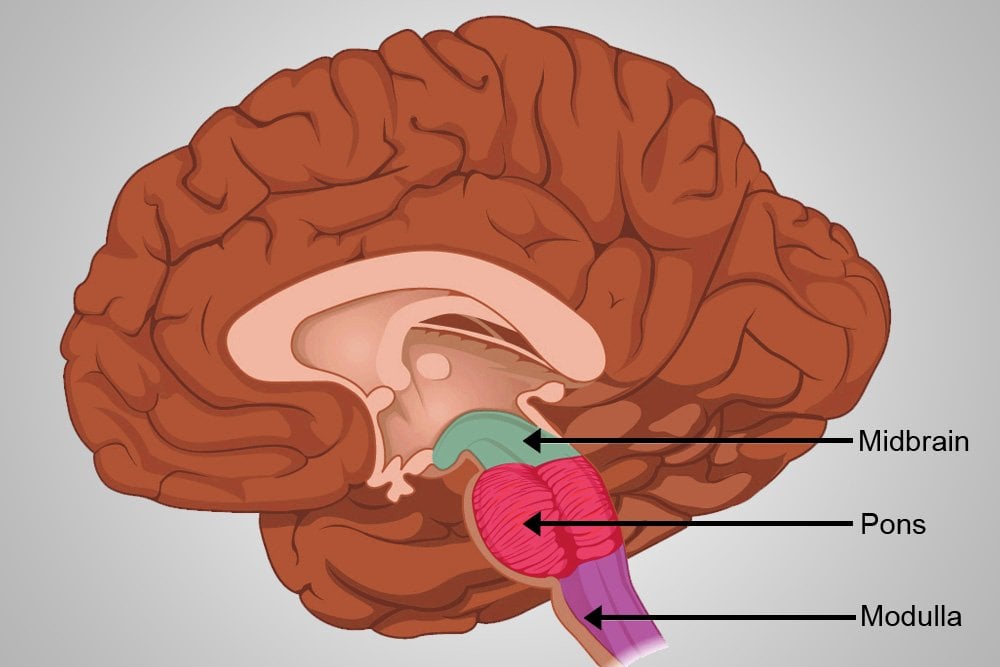

Medulla Oblongata: What It Is, Function & Anatomy

Know Your Brain: Medulla Oblongata

Medulla oblongata | Description, Anatomy, & Function | Britannica

Medulla Oblongata: Location, Function, Injury, and Illness

The Anatomy of the Medulla Oblongata

Medulla Oblongata Location, Function, and Features

Medulla Oblongata vs. Pons | Locations, Functions & Structures Video

The Medulla Oblongata and Pons

Surgical Anatomy of the Medulla Oblongata | SpringerLink